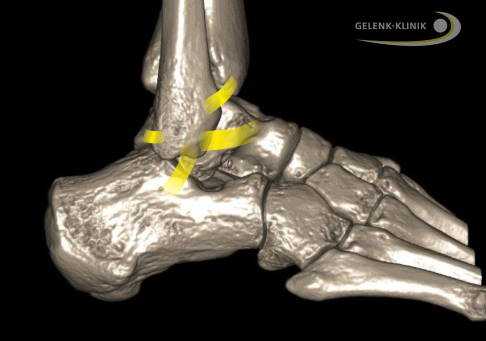

Отклонения оси в голеностопе появляются вследствие аварий либо неправильно сросшихся переломов таранной (Talus) либо пяточной (Calcaneus) костей. Другими причинами данной деформации могут стать разрывы внешних связок и растяжения.

Травмы стопы также могут спровоцировать начало данной патологии. Кроме того, смещения в голеностопном суставе могут появиться из-за внешней деформации пяточной кости, которая возникает вследствие плоско-вальгусной деформации.

Внешние связки соединяют малоберцовую кость (Fibula) с пяточной и таранной костями. Межберцовый синдесмоз проходит между большеберцовой и малоберцовой костями. © Gelenk-Klinik